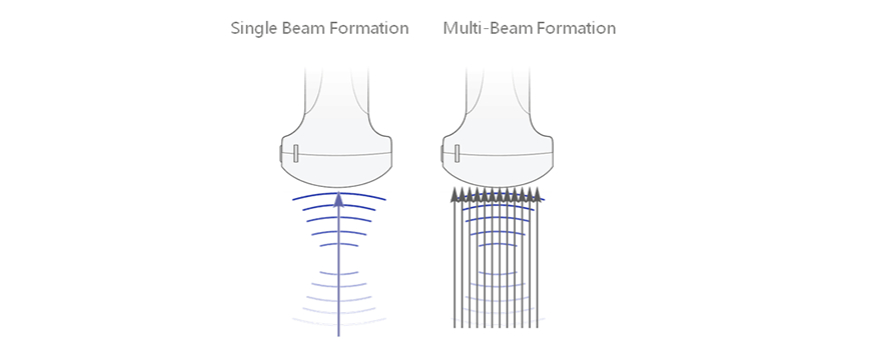

Multi-Beam Formation

Tot 12 keer meer frequente beeldvastlegging per doorgaande bundel, hetgeen resulteert in uitstekende tijdresolutie en een hoger framerate.